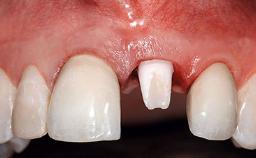

A 32-year-old female Caucasian patient with a compromised maxillary right central incisor was referred to us by a general dentist. Her chief complaints were discomfort and mobility of tooth 11 with unsatisfactory esthetics due to discoloration. The patient reported a previous trauma, some years earlier, as the origin of pathology on the afflicted tooth. Anamnesis was negative for any other dental or periodontal pathology in the remaining dentition. The patient did not take any medication and reported to be a light smoker (5–10 cigs/day). She had high esthetic expectations of her treatment. The extraoral examination revealed a high smile line with full exposure of her maxillary teeth and surrounding soft tissue in the area between the second premolars.

Replacement of an Upper Right Central Incisor with Root Resorption: Ridge Preservation, Delayed Placement of an NC Bone Level Roxolid Implant